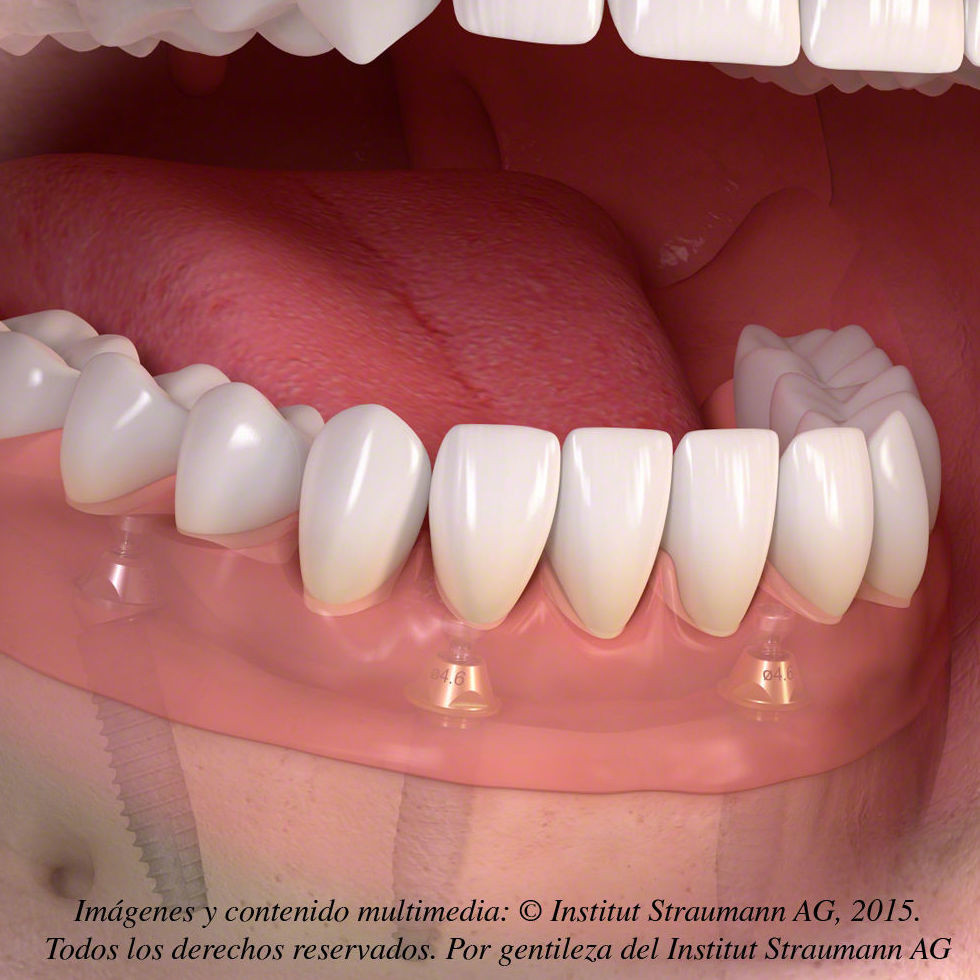

Sobredentadura. Es importante destacar que esta modalidad de tratamiento se perfila como una opción REMOVIBLE, es decir, una vez colocados los implantes (su número varía desde un mínimo de 2 a un máximo de 4 en la mandíbula y un mínimo de 4 en el maxilar) la prótesis se asentará y ajustará sobre ellos de una manera firme y estable, pero el paciente podrá retirarla siempre que lo desee. Relativamente voluminosa, la prótesis repone la totalidad de los dientes ausentes así como los tejidos perdidos como consecuencia del proceso de reabsorción ósea que se desencadena tras la pérdida dentaria.

Este tipo de tratamiento se recomienda, siempre que la disponibilidad ósea lo permita, a aquellos pacientes con un marcado grado de reabsorción ósea; la aleta vestibular de la prótesis les devolverá el soporte labial perdido.

Prótesis híbrida. Modalidad FIJA de tratamiento. A diferencia de la anterior, el paciente no podrá retirarla, será el odontólogo el encargado de hacerlo siempre que fuese necesario. Exige un mínimo de 4 hasta un máximo de 6 implantes en la mandíbula y un mínimo de 6 implantes en el maxilar. La prótesis irá directamente atornillada a los pilares, reponiendo la totalidad de los dientes ausentes y mínimamente los tejidos perdidos.

Este tipo de tratamiento se recomienda, siempre que la disponibilidad ósea lo permita, a aquellos pacientes con un leve grado de reabsorción ósea, siempre y cuando la línea de sonrisa del paciente no sea demasiado alta debido al riesgo de mostrar la transición entre la prótesis y la encía. De ser este el caso, funcionalmente podremos hablar de éxito, pero nunca desde un punto de vista estético.

Prótesis fija. Como su propio nombre indica, se trata de una modalidad FIJA de tratamiento. Exige un mínimo de 6 hasta un máximo de 8 implantes en la mandíbula y un mínimo de 6 hasta un máximo de 8 implantes en el maxilar. La prótesis podrá ir atornillada o cementada, reponiendo EXCLUSIVAMENTE la totalidad de los dientes ausentes.

Este tipo de tratamiento se recomienda, siempre que la disponibilidad ósea lo permita, a los pacientes recientemente desdentados (sin grado de reabsorción ósea) que no necesiten soporte labial porque éste se ha conservado y la línea de sonrisa sea media. Líneas de sonrisa altas implicarían, como en el caso anterior, un riesgo estético elevado al mostrar la transición entre la prótesis y la encía.